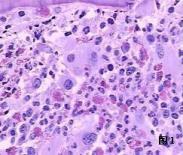

骨髓纖維化

骨髓纖維化

骨髓纖維化

628健康網為您分享有關骨髓纖維化的癥狀,骨髓纖維化的治療方法,骨髓纖維化的預防知識,骨髓纖維化的癥狀圖片,骨髓纖維化...